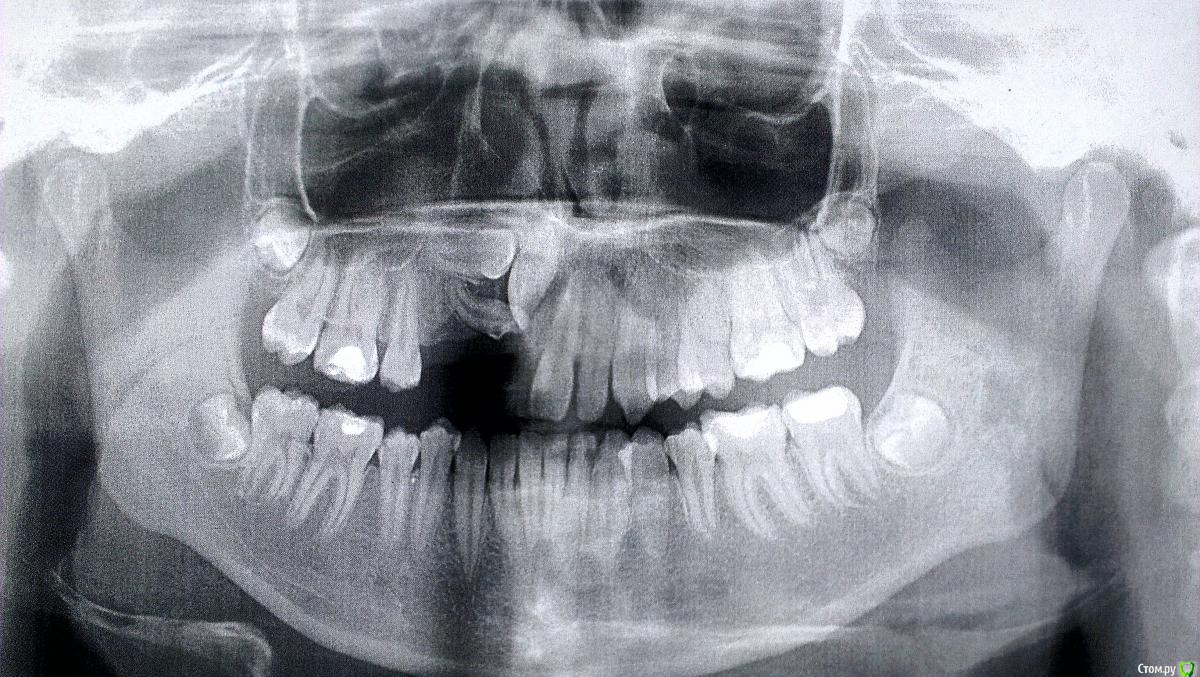

Солнечный СВЕТ Опубликовано 15 февраля, 2015 Поделиться Опубликовано 15 февраля, 2015 Девочка 14 лет, зубы не прорезались,у девочки уже комплекс,родители тоже не знают что делать,готовы ехать в другой город только бы помог кто нибудь,сейчас носит чсп,какие возможны варианты лечения и куда можно обратиться чтобы смогли помочь?!?!?!?! Ссылка на комментарий

SDC Опубликовано 15 февраля, 2015 Поделиться Опубликовано 15 февраля, 2015 (изменено) Ориентировочный план: 1-е посещение : консультация с КТ и слепками (принятие решения о том в какой последовательности вытягивать зубы) скорее всего, возможно по моделям и КТ без пациентки. 2-е посещение: начало лечения, будет начинаться с раскрытия и диагностического вытягивания ретинированных зубов (последовательность будет ясна после диагностики КТ). Аппарат для диагностического вытягивания: скорее всего кантилевер. В среднем плановые визиты на 1м этапе : 1-е с периодичностью в 1,5-2 месяца. После положительной динамики выдвижения ретинированных зубов, переход на полную брекет-систему. Изменено 15 февраля, 2015 пользователем SDC Ссылка на комментарий

Molox Опубликовано 28 февраля, 2015 Поделиться Опубликовано 28 февраля, 2015 Полностью согласен насчет кт, но оптимизма мало. По итогу можно получить неслабые карманы в области этих зубов, т.к. низкий уровень кости. Ссылка на комментарий

krokomot Опубликовано 28 февраля, 2015 Поделиться Опубликовано 28 февраля, 2015 (изменено) ничего подобно не произойдет если все делать правильно, но возможно, что головоломка и не сложится, хотя складывались и не такиеобязательно :наладить гигиену,сделать модели и ктфиксация системывытяжениеПорядок время и последовательность определяться после изучения кт и моделей. Изменено 28 февраля, 2015 пользователем krokomot 1 Ссылка на комментарий